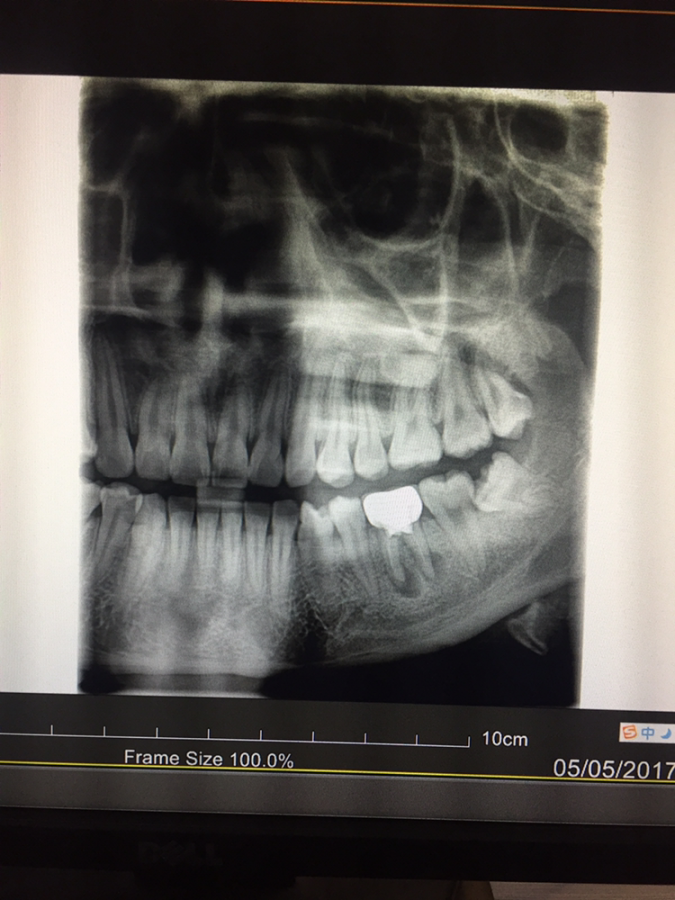

您好,我的左下第六颗牙齿约在两年前做了根管治疗并带上牙冠,一直相安无事。这两天突然开始疼痛,做了牙片后发现牙根尖处发炎严重,医生说根管再治疗难度高成功率也低,可以考虑拔牙,请问我该如何抉择呢?期待您的回复,谢谢! 发自小木虫IOS客户端 |